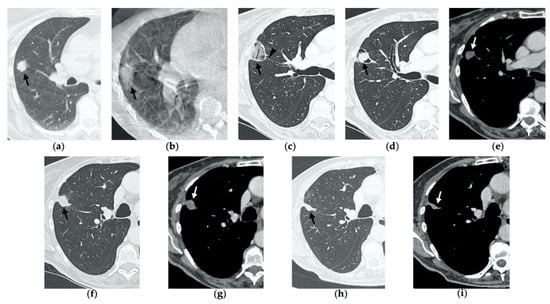

Tomography 08 00051 g006

Figure 7. 68-year-old man with a biopsy-proved squamocellular carcinoma in the left upper lobe. (a) Axial CT before treatment. (b) Cone-beam CT image at the end of MWA shows a wide GGO area (black arrow) among the ablation site. (ce) Since persistent hydro-pneumothorax on chest X-rays is detected, CT without contrast administration is performed before the usual 1-month follow-up; axial and sagittal CT images show a large consolidation with central cavitation (black arrow); on a different level, a concomitant hydro-pneumothorax is evident (arrowhead); the diagnosis of broncho-pleural fistula is made. (f,g) Sagittal 2-month follow-up CT images show a decrease in size of the cavitated consolidation and hydropneumothorax; a communication between a bronchus and the pleural cavity is evident (black arrow); (f) the consolidation shows no contrast enhancement (white arrow). (h) Axial 4-month follow-up CT image shows a decrease in size of the consolidation with complete resolution of both cavitation and pneumothorax (black arrow).

5. Early Complications

The most common complications to consider after lung MWA are pneumothorax (38%), pleural effusion (3–6%) and parenchymal hemorrhage (3–6%), which in most cases present a benign course without any consequences for the patient [7,10,14,21,25]. Since these represent frequent findings in clinical practice in most hospitals, we decided to describe a rare complication (0.5%) that often risks being overlooked: bronchopleural fistula (BPF) [25].

BPF is defined as communication between a bronchus and the pleural space through the ablation zone (Figure 6e,f). The management of this complication is challenging, since treatment may require insertion of a percutaneous drainage or eventually surgery, bronchoscopic or interventional procedures. As a result, BPF represents an extremely rare though potentially severe complication and it should be suspected in cases of delayed or persistent pneumothorax, detected with chest X-ray, respectively, during early and late follow-up CTs (Figure 7) [26].

BPF commonly occurs with hydropneumothorax, and it should not be mistaken with a bronchial fistula, which is a communication between a bronchus and a cavitation in the ablation area and usually resolves uneventfully [26].